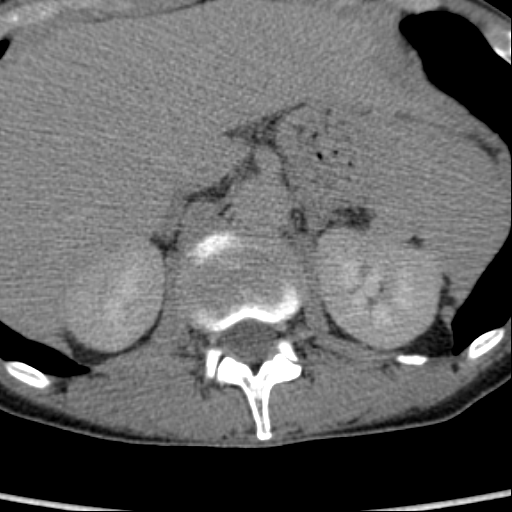

Обнаружилось небольшое образование низкой плотности, с достаточно ровными, четкими контурами парааортально справа около ножки диафрагмы на уровне тела L1 позвонка.

При нативе плотность 6HU, паренхиматозная - 18-20HU, экскреторная (15 минут) - 60-65HU.

Выкладываю по очереди срезы на одинаковых уровнях, сначала паренхиматозная, потом отсроченная фазы.